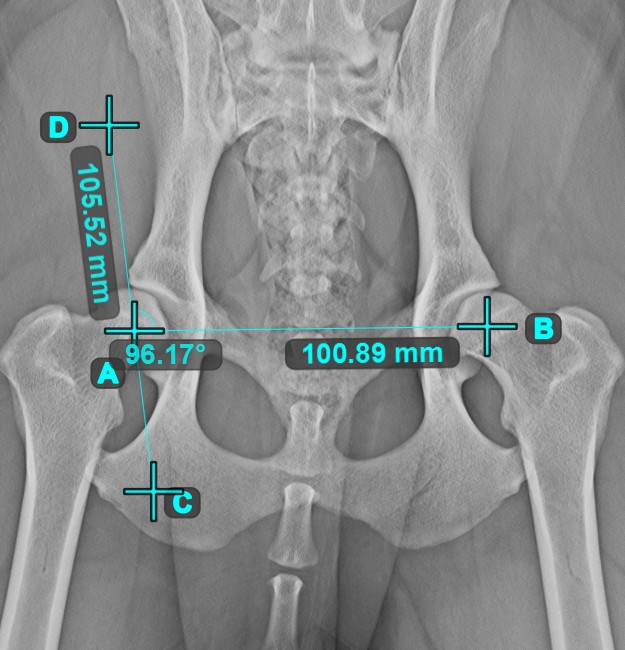

Line Measurement¶

Select the Line Measurement

tool and assign it to one of the available mouse buttons. Place the start and end points on the scene or select them from already existing points on the image. The distance between the two points will be automatically

calculated by using the default calibration data, or the recalibrated data by the length calibration measurement.

Angle of Lines¶

Select the tool from the left toolbar and assign it to one of the available mouse buttons. Start by selecting the first line from the ones already drawn on the scene, or place the start and end points to create the line. Follow the same steps for the second line of the measurement. The angle between the two lines will be automatically calculated.

Modify the start and end points of both lines by using the Select/Move Item

tool. The angle between the two lines will be automatically recalculated.

Angle from 3 Points¶

The Angle from 3 Points

tool is a simple and effective way to calculate an angle from just three points.

Start by selecting the tool from the left toolbar and assign it to one of the available mouse buttons. Place the start point of the initial side, the vertex, and the end point of the terminal side of the angle, or select the points from the scene. The sides of the angle will be automatically constructed, thus calculating the angle between the lines.